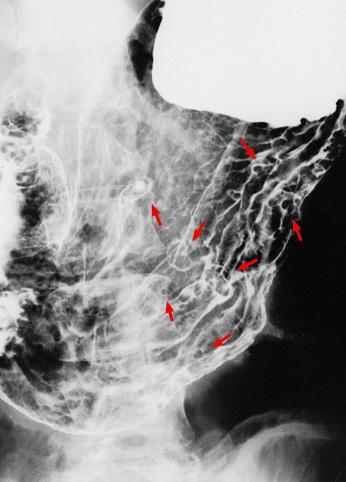

Peutz-Jeghers증후군

소장진행암을 동반한 Peutz-Jeghers증후군

종양양 병변/Peutz-Jeghers증후군

위(부위)/2개 이상

X-P

10~14